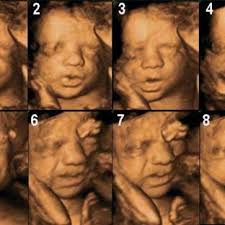

When Is It The Best Time To Do A 3d 4d Ultrasound December 2018 Babies Forums What To Expect

When Is It The Best Time To Do A 3d 4d Ultrasound December 2018 Babies Forums What To Expect from images.agoramedia.com